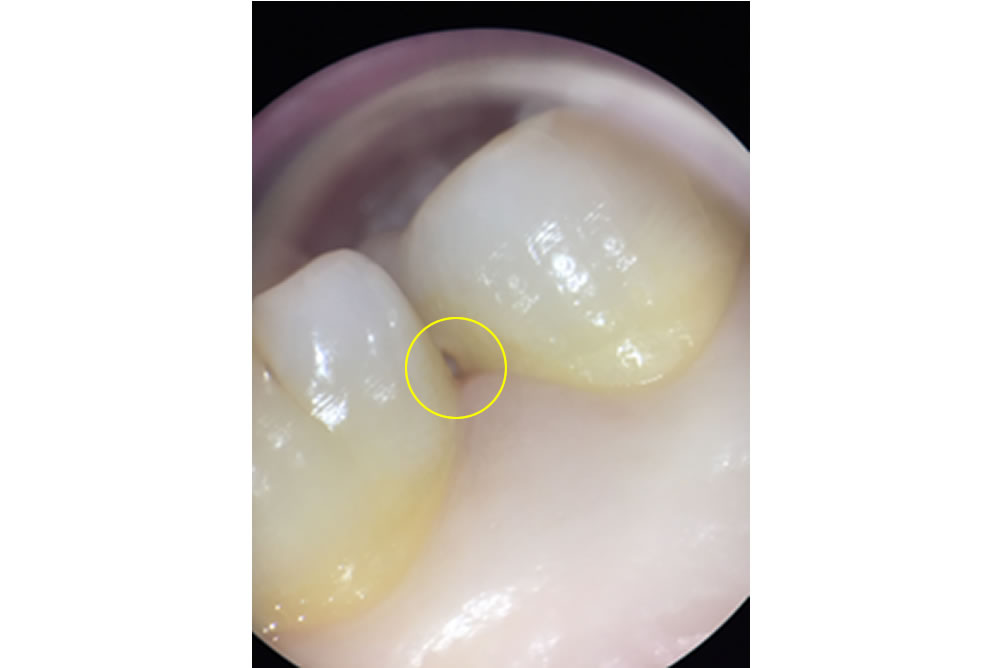

Case1 歯と歯の間のフロスが引っかかる

マイクロスコープ(顕微鏡)で確認すると、丸部分に段差があることが分かります。肉眼では分からないものも、マイクロスコープ(顕微鏡)で確認することによって、むやみに削ることなく治療が行えます。